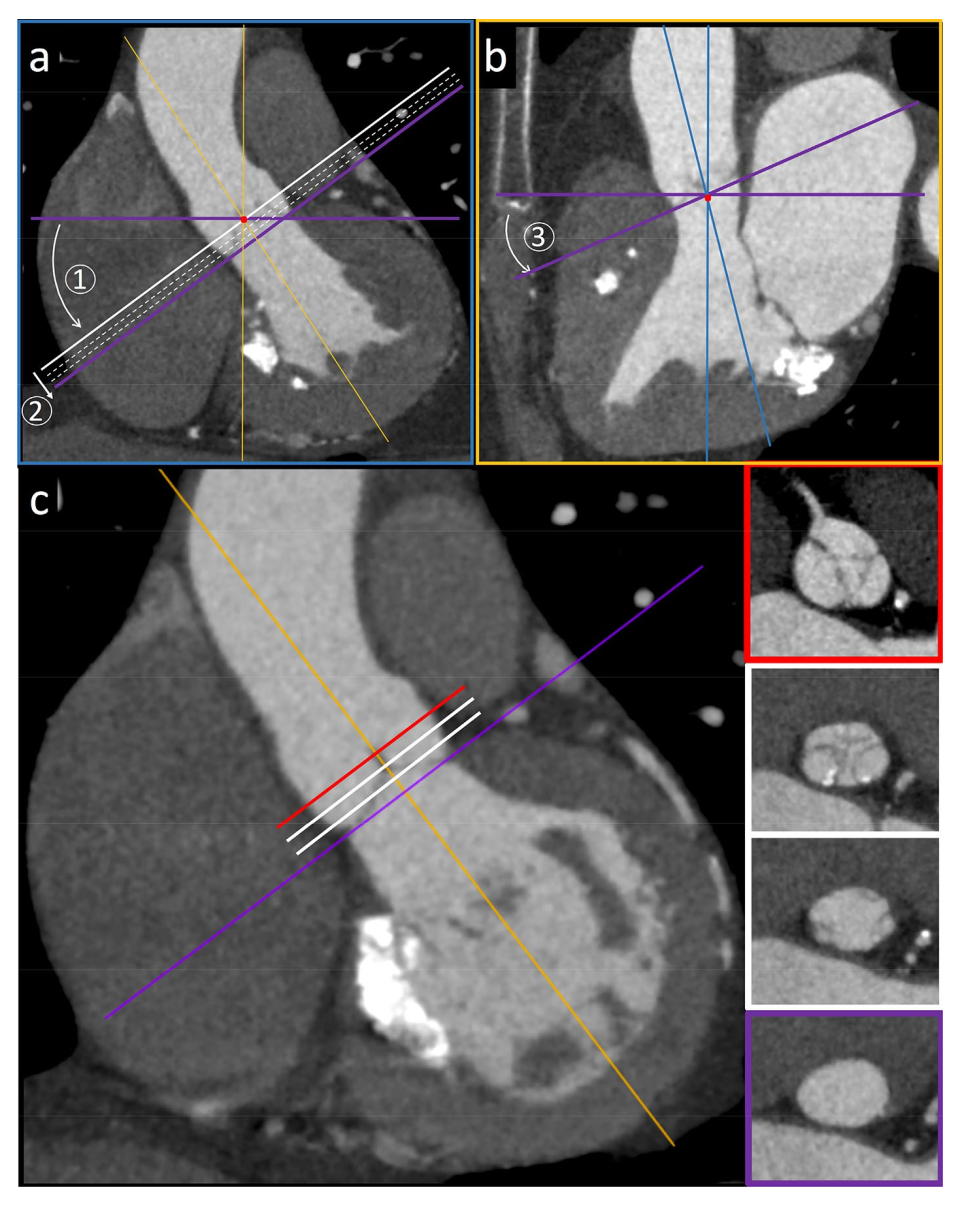

图1: 通过正交的三维重建图像(如3D VR图像(a, c, e, g)所示)测量不同解剖水平的主动脉管腔尺寸,分别为主脉瓣环(a, b), Valsalva窦(c, d),窦管交界处(e, f),升主动脉中点处(g, h)以及测量窦管交界处的高度(i, l)。

图2:使用普通显示器(通常同时看到三重投影)对主动脉环平面进行多平面重建的说明。加载 CTA 数据集后,将冠状图像滚动到穿过主动脉中心的图像平面(a)。在冠状图像中,将轴向观察平面(水平紫色线)移动到通过主动脉瓣中心的平面的水平。通过将旋转中心(红点,旋转轴之间的交汇点)放置在瓣膜区域的中心,旋转轴向平面(步骤 1)直到它完全平行于通过瓣环的平面(白线),然后将轴向平面的参考线向后移动(步骤 2),直到它通过主动脉瓣的铰接点(倾斜的紫色线)。与轴向观察平面成 90° 的矢状面(橙色参考线)将相应倾斜。在新生成的斜矢状面 (b) 上,将轴向参考线(水平紫色线)旋转(步骤 3),直到它通过主动脉瓣的前方和后方的最低插入点。滚动刚刚定向的新斜轴平面 (c) 可使穿过瓣环的平面(紫色框)、穿过尖瓣插入物(白框)和 Valsalva 窦的平面(红色框)可视化 。

主动脉根部尺寸评估

主动脉根部连接心脏和体循环,是一个复杂而精密的结构,由瓣环、主动脉瓣、Valsalva 窦和窦管交界处组成。在 CT 图像上,主动脉瓣环是对应于主动脉瓣基底部的解剖部位,三个瓣叶的最低插入点(铰链点)形成的环平面,位于心室-动脉交界处的正下方。准确测量主动脉瓣环和主动脉根部是评估TAVI可行性、正确的术前计划和装置选择(瓣膜尺寸和设计)的基础。沿常规解剖平面(冠状面和矢状面)重建或单斜重建粗略测量瓣环尺寸是不可行的。为得到可靠的测量结果,必须提供最佳质量的图像以及对重建斜面的正确定位,这是装置选择的基础。图2显示了如何从传统平面开始采用双斜入路获得主动脉瓣环的正确横截面图像。瓣环尺寸测量需要标准化和可重复的方法。瓣环尺寸的测量应包括长轴和短轴直径、截面积和周长(图3),所有测量值都可通过(半)自动衰减/基于Hounsfield 单元的轮廓检测得到。面积和周长得出的有效直径是在植入装置后瓣环为正圆形的几何假设下计算的。然而,这些方法存在固有误差,并且当瓣环形状特别偏心时,可能导致所选假体尺寸过小或过大,从而导致瓣周漏或植入的瓣膜展开不完全的风险。瓣环在心动周期中也会发生构象和尺寸变化:其形状在收缩期更偏圆形,在舒张期主要呈卵圆到椭圆形。由于与左心室射血相关的径向力的增加,与舒张期相比,收缩期瓣环的短轴直径、截面积和周长更大。因此,如果可获得多相数据,应首选在收缩期重建的图像来测量瓣环尺寸,因为在不同时相变化很大的患者中,使用舒张期测量可能会导致 TAVI 假体尺寸过小,导致瓣周漏的风险增加(图 4)。然而,在心率较快或心律失常的患者中,收缩期图像更容易受到心脏跳动伪影的影响,如果在扫描采集期间进行剂量调制,则通常会表现为图像噪声增加。在这些情况下,舒张期图像会提供更好的图像质量。主动脉瓣狭窄通常以瓣叶上不同程度的钙沉积为特征,钙沉积量随狭窄程度而增加,提示预后较差。特别是钙化性主动脉瓣狭窄的患病率随着年龄的增长而增加,在年龄 > 65岁的患者中达到峰值,这是最常接受TAVI的人群。主动脉瓣钙化程度可以通过 CTA 图像进行主观定性评估(无、轻度、中度和重度,图5),但是基于ECG门控的非增强CT 图像的Agatston 评分系统已被提议用于定量评估和术前风险分层,最常用的鉴定严重主动脉狭窄的阈值是男性 2000 、女性 1200。瓣膜钙沉积的分布应根据分布模式(对称/不对称、弥漫/局灶)、相对于瓣叶(瓣叶边缘、连合处和附着点)和 LVOT 的位置进行常规描述。当输送系统打开时,钙化的天然瓣叶被挤压到主动脉壁上。许多研究表明,无论是使用自膨瓣或球扩瓣,装置落脚区(landing zone)的钙化程度及分布模式对TAVI 后的手术结果有显着影响。主动脉瓣的大块或偏心钙化可能会妨碍假体的完全打开或正确锚定。事实上,附着在瓣叶边缘或连合处的钙化结节会造成机械障碍,从而导致人工瓣膜与主动脉根部之间存在残余间隙,这可能会影响植入的人工瓣膜的稳定性、对锚定部位的粘附性并使装置部分变形。严重的瓣膜钙化,特别容易增加术后反流或瓣周漏的风险,导致患者难以耐受的压力超负荷。主动脉瓣的严重钙化也已知与其他并发症有关,例如球囊扩张时引起瓣环破裂,因为主动脉环钙化使瓣环刚性增加、形变能力降低、传导障碍或钙化栓塞。与严重瓣膜钙化相关的另一个潜在风险是冗长而钙化的主动脉瓣易引起的冠状动脉开口阻塞。在 TAVI 中,自身瓣叶(包括任何粘附的钙化灶或赘生物)不会像外科瓣膜置换术那样被移除,而是在假体瓣膜释放过程中移位并被压在天然主动脉壁上。自身瓣叶重叠而阻塞冠状动脉开口是 TAVI 手术的一种罕见却危及生命的并发症,发生在 0.35-0.8%之间,最常见于接受球扩瓣的患者,并且通常影响左冠状动脉。此种情况下通常需要经皮冠状动脉介入治疗。尽管文献报道的冠脉介入可行性和成功率很高,但短期和长期死亡率仍然很高。较低的冠状动脉开口、浅Valsalva窦、严重钙化和较长的原生主动脉瓣叶是易引起冠脉开口阻塞的解剖情况,因此详细的术前解剖评估对于最大限度地降低这种并发症的风险至关重要。所以需要在CT 图像上测量从主动脉瓣环平面到每个冠状动脉开口下缘的纵向距离,具体方法为收缩期在斜冠状位上应用合适定向的多平面重建(图 6)。通常认为冠状动脉口和瓣环之间的距离大于10-14毫米时发生冠状动脉阻塞的风险较低,但是更短的距离也并未被严格认定为 TAVI 的排除标准,这些测量值应与主动脉瓣长度结合考虑。就算冠状动脉口和瓣膜平面之间有足够距离,若存在瓣膜尖的重度和弥漫性钙化也要特别注意。评估还应包括在双斜投影上测量 Valsalva 窦水平的主动脉根部的横向直径和高度,因为要正确摆放特定的 TAVI 装置需要测量最小窦宽度和高度值,这因型号而异。应探查 LVOT 以验证落脚区可行并排除瓣膜下阻塞,特别是在经心尖入路的情况下,并验证是否存在钙化;在这种情况下,最好使用自膨瓣。进一步的常规测量应包括评估窦管交界处和升主动脉最大和最小直径(通常为主动脉环上方 50 毫米)。